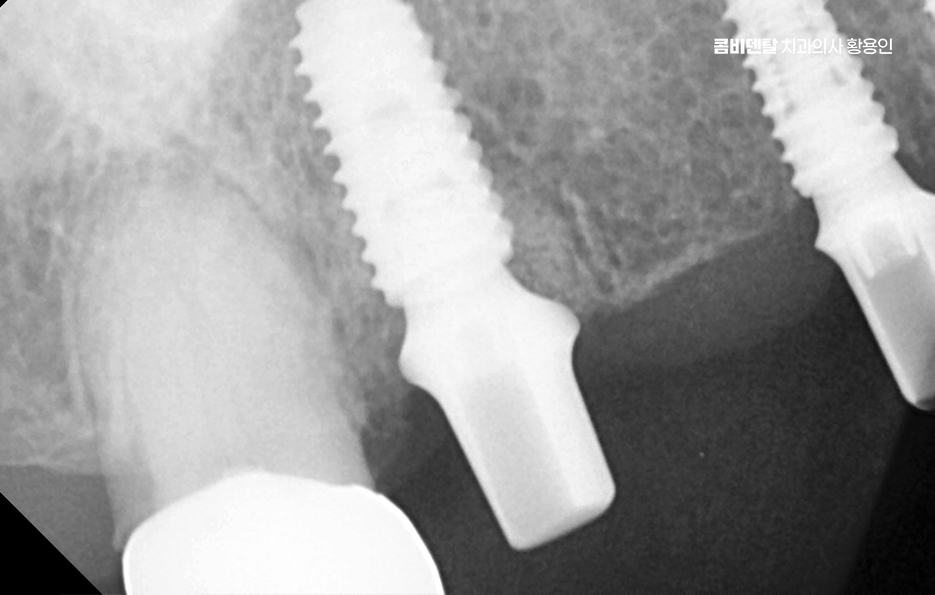

이러한 문제를 막기 위한 효과적인 방법이 바로 임플란트 치료로 어금니 임플란트를 계획할 때는 먼저 잇몸뼈 상태를 정밀하게 확인해야 하며 3D CT 촬영을 통해 뼈의 높이와 두께, 그리고 임플란트를 심을 수 있는 공간을 세밀하게 분석해야 하며 위턱 어금니 같은 경우 상악동이라는 빈 공간이 바로 위에 있어서, 치아가 빠지고 나면 그 공간이 아래로 내려와 임플란트를 심을 자리가 부족해지는 경우가 많고 아래턱 어금니는 하치조신경이라는 중요한 신경이 지나가기 때문에, 신경을 피해서 정확한 위치와 각도로 식립하는 계획이 필요할 수 있어요

어금니는 심미성보다는 저작력을 우선하기 때문에 내구성이 높은 구조로 설계하게 되며 치료가 끝났다고 해서 끝이 아니라, 정기적인 유지관리와 스케일링, 임플란트 주위염 예방을 위한 위생 습관이 반드시 동반돼야 하고 특히 어금니는 입 안 깊숙한 곳에 위치하기 때문에 칫솔질이 어렵고, 음식물이 잘 끼기 때문에 워터픽이나 치간칫솔을 병행해서 관리하는 것이 장기적인 치료 성공과 유지에 있어서 관건이라 할 수 있었어요

결론적으로 어금니 임플란트를 하지 않고 방치하면, 단순히 어금니 하나의 문제가 아니라 전체 교합, 반대편 치아, 나아가 턱관절 기능과 소화 건강까지 영향을 주게 되기 때문에, 가능한 빠르게 치료를 결정하는 것이 장기적으로 더 많은 비용과 시간을 절약하는 방법이 되는 거예요. 특히 뼈가 아직 충분하고, 주변 치아가 건강할 때 임플란트를 진행하면 예후도 좋고, 추가적인 뼈이식이나 부가 수술 없이도 비교적 간단하게 치료가 가능한 경우가 많아서 어금니 상실 후에는 임플란트 치료와의 연계를 잘 고려해서 치료 계획을 늦지 않게 세우시길 바라고 있어요